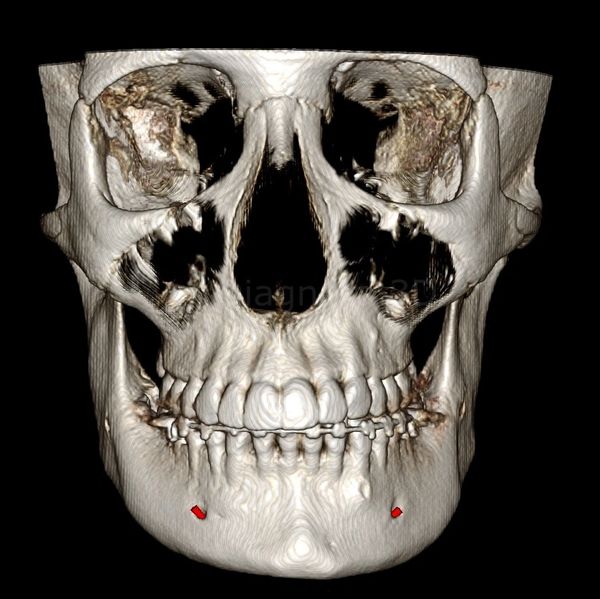

3D Anterior view of the Maxillofacial Skeleton